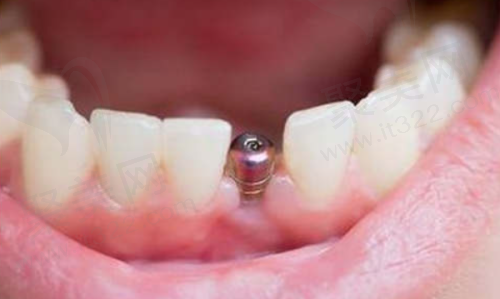

在三亚,牙齿缺失的朋友们常常会问:“三亚种植牙多少钱一颗?”这个问题可没那么简单,因为种植牙价格受到多种因素影响。2025 年,三亚种植牙市场有了新变化,单颗种植牙 2990 元起,这给不少人带来了希望。接下来,咱们就详细唠唠三亚种植牙价格的那些事儿,涵盖不同医院、不同种植体品牌的价格情况,以及影响价格的各种因素,让大家心里有个底。

在三亚,种植牙价格一般在 5000 元到 20000 元这个区间。不过呢,这只是个大概范围,具体价格得看种植体品牌、手术复杂程度、医生资质等因素。就好比买手机,不同品牌、不同配置,价格肯定不一样。所以啊,没有所谓“更好”或者“较便宜”的单一标准,得结合个人口腔条件和需求来综合评估。